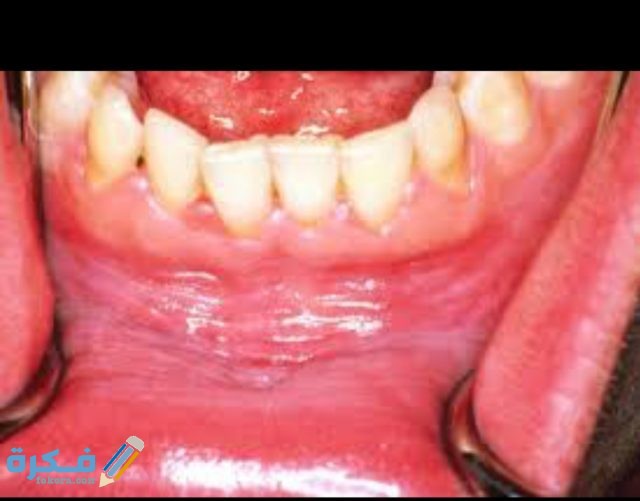

شرح خطوات علاج التهاب اللثة الحاد في المنزل

سوف نتحدث في هذا المقال من خلال موقع فكرة blog.seha.fakera.com عن كيفية علاج التهاب اللثة الشديد في المنزل ، حيث يصاب بعض الأشخاص في بعض الأحيان بالتهاب اللثة الشديد ويعجزون عن الذهاب الى الطبيب وبالتالي يبَحثون عن كيفية علاج التهاب اللثة دون الخروج من المنزل وهذا ما سنتعرف عليه في هذا المقال .

- هناك بعض الأسباب المختلفة التي تسبب التهاب اللثة الشديد وأحيانا ينتج عن هذا الالتهاب حدوث النزيف ومن هذه الأسباب ما يلي:

- عدم غسل الأسنان بانتظام يؤدي الى تراكم الترسبات على الأسنان واللثة مما يعمل على التهابها .